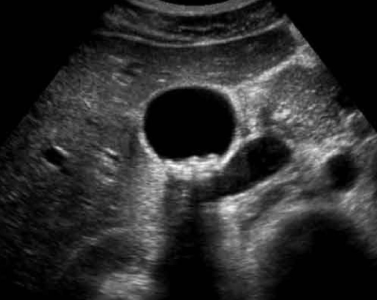

¿Para qué sirve USG?

*Permite ver presencial de litos (sombras posteriores)

* Ancho de vesícula (3-6 mm hasta 9mm) 10 mm es dilatado

* Grosor de pared (3-4mm)

* Nos dice como está páncreas, colédoco, , hígado, más vía extrahepática